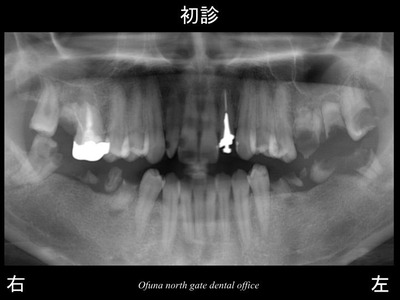

以下は初診時のレントゲンです。

いつも見ている方には みなれたことと思います。

始めて見られる方のために 簡単に以下のレントゲンの見方

について説明します。

以下のレントゲンの下に 右、左と書いてありますが、

当然のことながら 右と書いてあるのが“ 右側 ”です。

実際の左右とは違いますので、今後見られる時にはご注意下さい。

虫歯がいっぱいあることが分かるかと思います。

このように多くの虫歯がある方がいらっしゃいます。